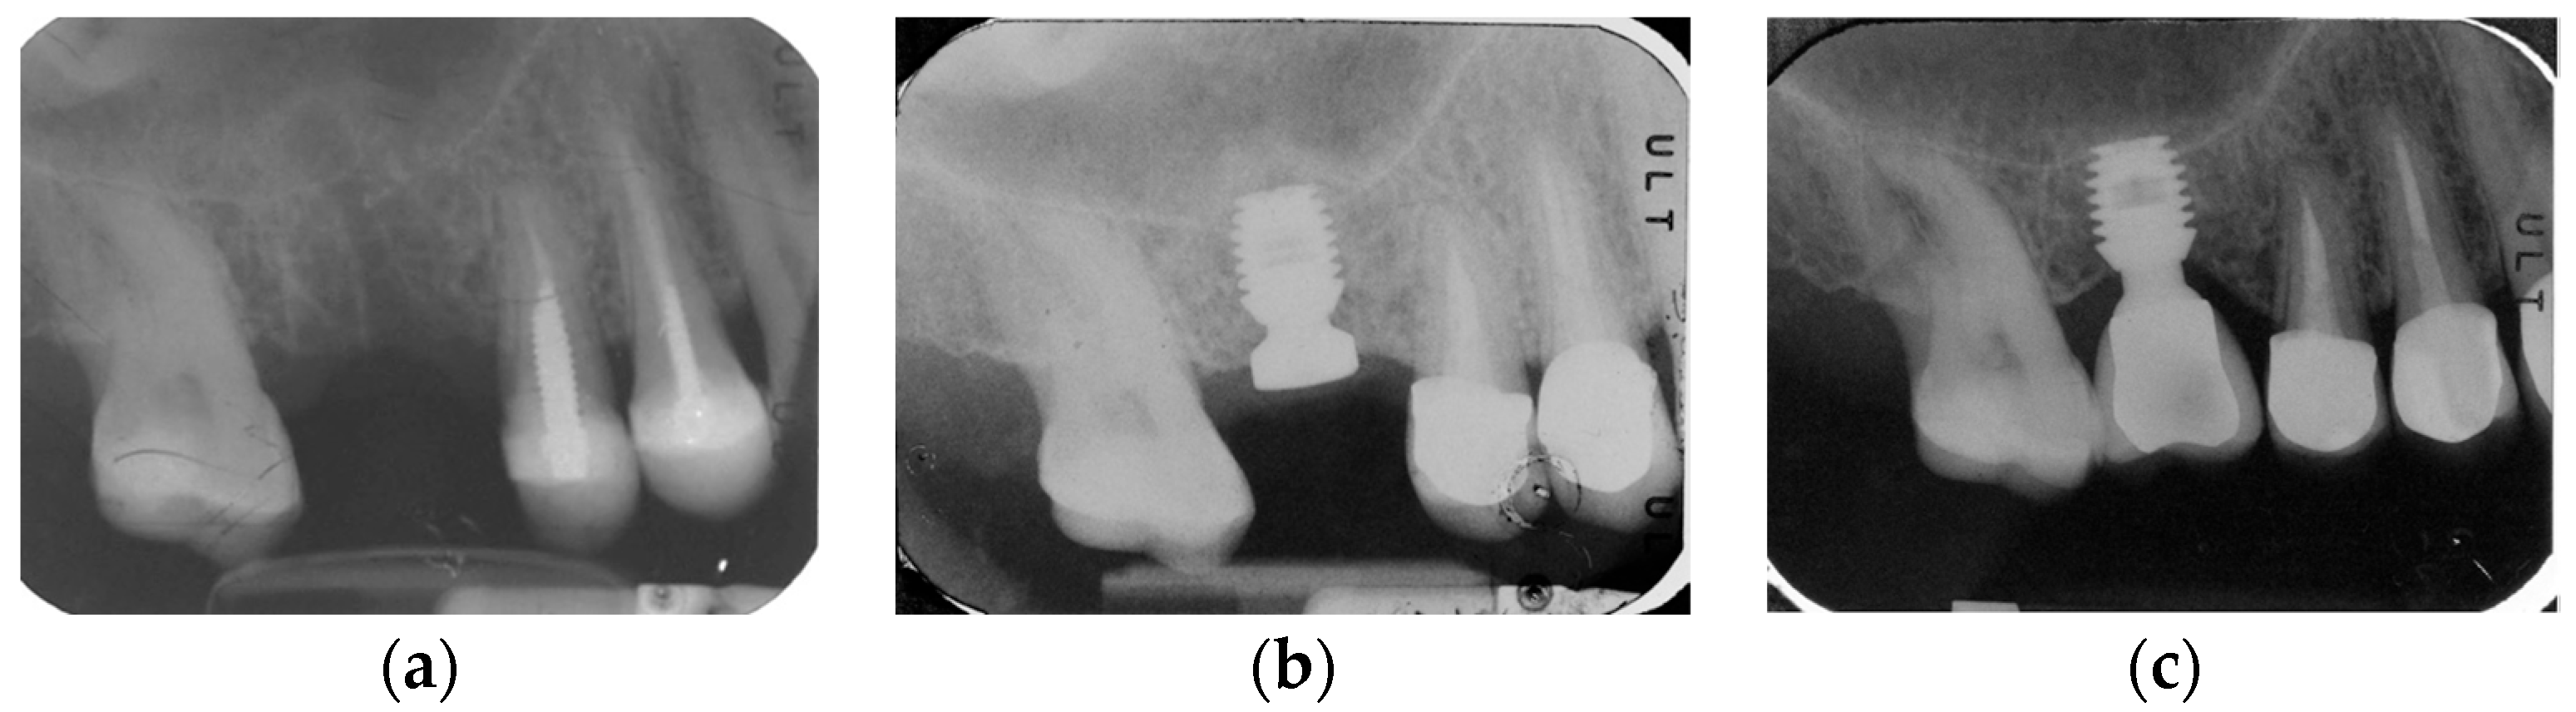

2.2. Surgical Protocol